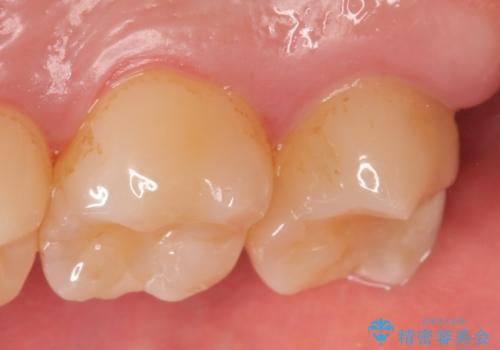

その後オールセラミッククラウンによる補綴を行いました。

今回用いたオールセラミッククラウンはジルコニアフレームという白い素材の上にセラミックを盛っているため、審美性が非常に高いのが特徴です。

また、ジルコニアは人工ダイヤモンドの材料にも使われているほど高い強度を持っており、そのためオールセラミッククラウンは審美性だけでなく、奥歯やブリッジの補綴も可能とするクラウンです。